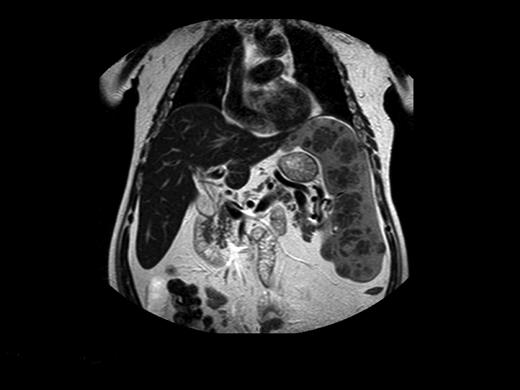

Despite advocating elimination of BM aspiration for the sole purpose of GD diagnosis, there are valid indications for this examination in GD, all related to associated diseases. (1) When the clinical presentation is atypical and differential diagnosis includes entities that can be identified/excluded by BM smear such as idiopathic thrombocytopenic purpura or acute leukemia. There are invariably patients who have 2 independently sorting disorders at presentation, such as GD and a hematologic malignancy (eg, one of our patients had a monoclonal IgA peak on routine work-up for GD; another with severe pancytopenia had acute myelogenous leukemia; Figure 1) and for whom BM examination will pinpoint the diagnosis/diagnoses. (2) When there is an unexplained deterioration in blood counts despite ERT in a symptomatic patient, or acute deterioration in a heretofore stable untreated patient, BM examination may show/exclude hematologic pathology. (3) When there is no response to ERT.

Acute myelogenous leukemia in a patient with otherwise asymptomatic GD. The Gaucher cells are indicated by arrows. Courtesy of Drs Ginette Shibi, Iris Barshack, and Hannah Maayan, Sheba Medical Center, Tel-Hashomer, Israel.